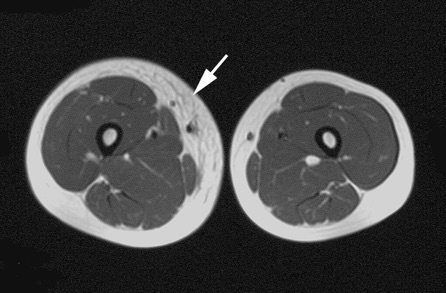

MR検査を行なうと、病変がより正確に分かりますが、その診断には、経験を必要とします.下の画像は、反対側の正常下肢と比較すると分かり易いです.

矢印はKTSの患者さんの右下腿、皮下脂肪層に静脈・リンパ系の異常が認められます.

矢印は、静脈性血管奇形の患者さんの右大腿部、筋肉内に病変があります.

矢印はリンパ浮腫の患者さんの右大腿部、皮下脂肪層にリンパ系の拡張が認められます.